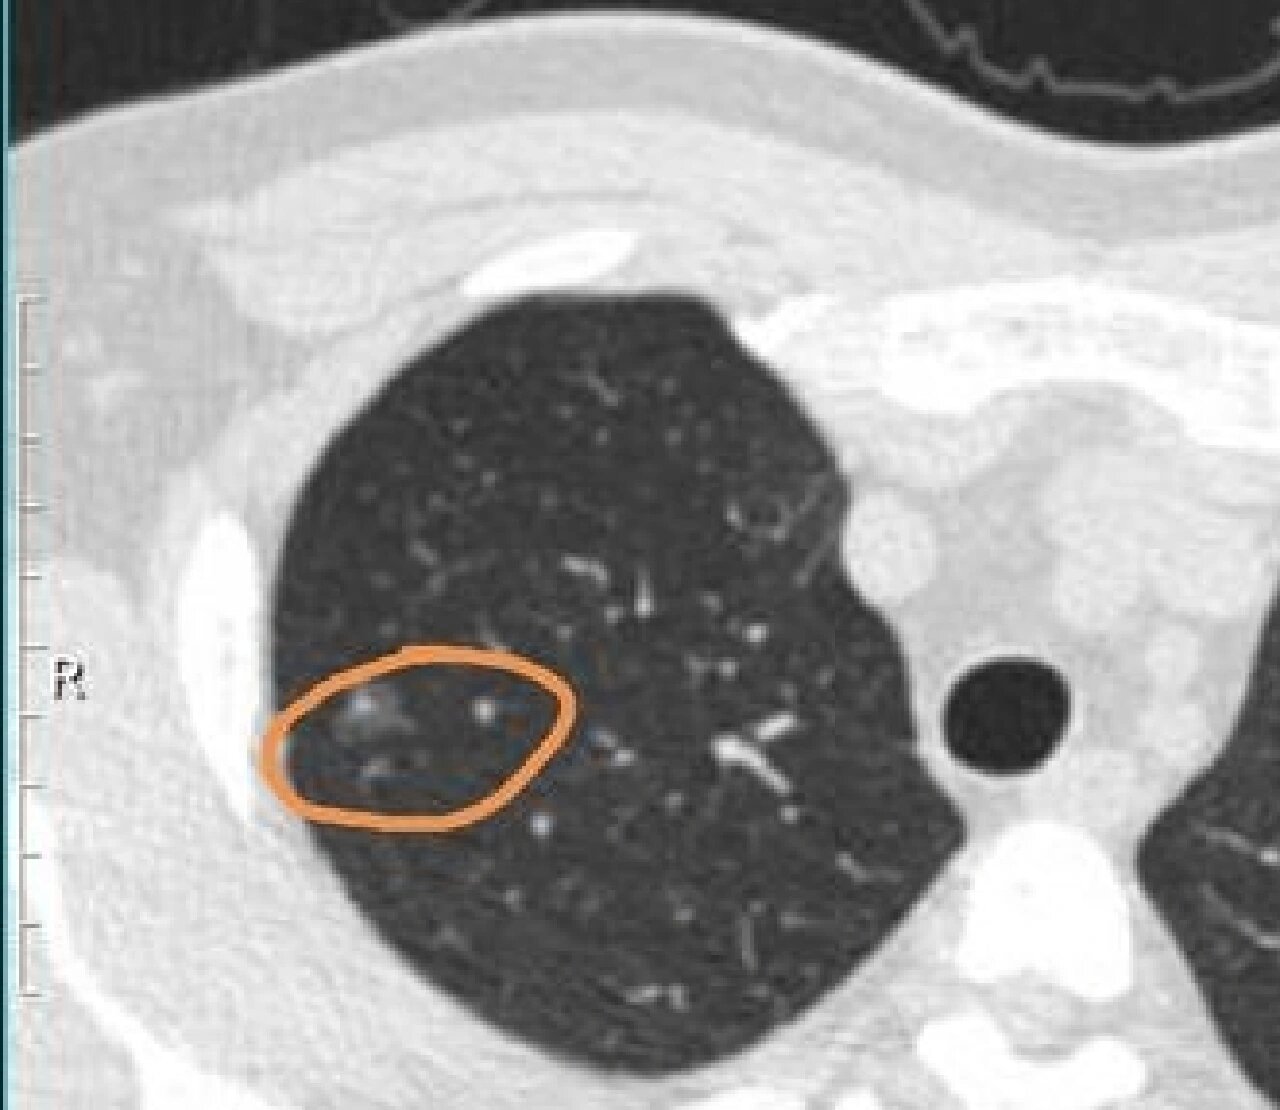

典型的右上肺腺癌的混合密度磨玻璃结节.